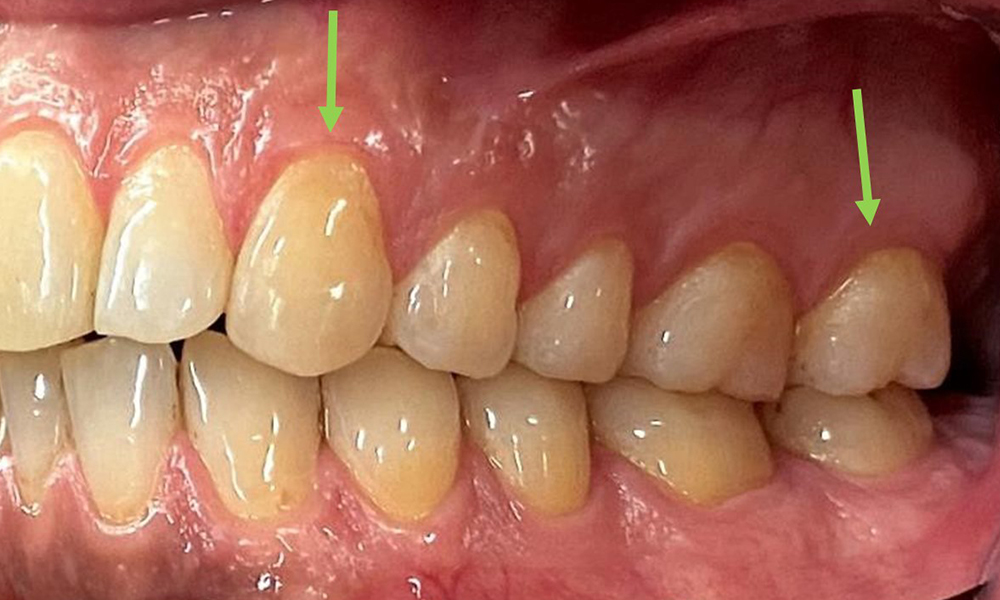

There were no pathological extraoral findings. During intraoral examination, inspection of the frontal view revealed brownish discolouration near the keratinised gingiva and at the transition to the moveable mucosa (Fig. 2), which could be attributed to nicotine consumption. Whitish mucosal lesions were observed on the palate, particularly near the maxillary molar palatal surfaces, indicating increased keratinisation and can also be attributed to nicotine consumption. The tongue was covered with a removable white and brownish coating.

The periodontal status should be thoroughly examined once a year. The detection of plaque using a staining agent may be a source of motivation. The assessment of intraoral findings, buccal surfaces and lingual mucosa are particularly important in smokers, as they will facilitate the detection of any pathological changes at an early stage (6). Photographic documentation allows the assessment of the development of potential pathological mucosal lesions over time. Referral to a specialist may be required to obtain and test tissue samples. Imaging procedures also support the motivational discussions with the patient. They may allow improvements to be highlighted over the course of subsequent preventive dental appointments.